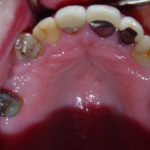

Case 6 – Upper Crowns / Lower Implants Makeover

- Before